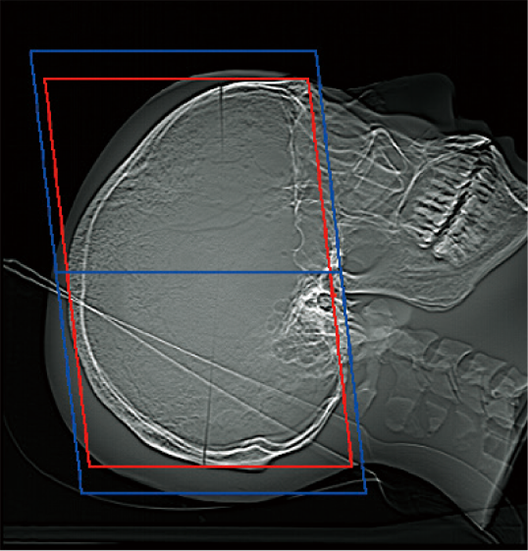

The scan range can be automatically set by the scanogram image. It is expected to improve reproducibility of scan position and efficiency of examinations, contributing to time reduction.

The scan range can be customized according to the operation of the facility since the margin of the scan range can be set in advance. The operator can also check and adjust the automatically calculated scan range.*7

OM Line

SM Line Head

RB Line

Chest

Red: Position set automatically

Blue: Position set automatically + set margin